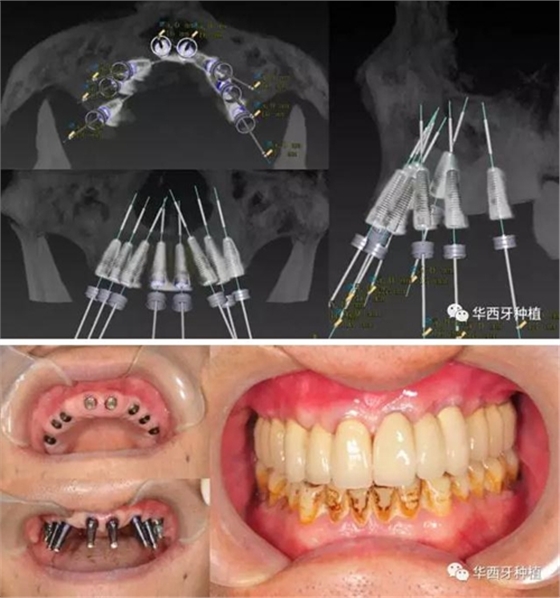

吳教授提到了使用數(shù)字化建模與導板的聯(lián)合應(yīng)用,不僅可以從設(shè)計上降低修復(fù)難度,便于在修復(fù)為導向的設(shè)計中種植體方向的確定,同時可以加入微創(chuàng)的手術(shù)方法,減輕術(shù)中創(chuàng)傷。

吳教授特別針對手術(shù)難度更大的all-on-four修復(fù)做了詳細的關(guān)于概念、設(shè)計、操作、修復(fù)的描述,首先是針對難度最大的手術(shù)環(huán)節(jié),就解剖、微創(chuàng)操作分別加以闡述。將他自己在臨床工作中的寶貴經(jīng)驗分享給了大家。

對于傳統(tǒng)的all-on-four術(shù)式,吳教授加入了微創(chuàng)的指導思想,設(shè)計時同樣加入數(shù)字化三維重建與修復(fù)一體化設(shè)計,增加了手術(shù)的可控性,同時極大減輕了患者的創(chuàng)傷程度,縮短了修復(fù)周期。

但是,他同時提到了此種修復(fù)方式操作難度要求很高,僅適合有經(jīng)驗的種植醫(yī)生操作。